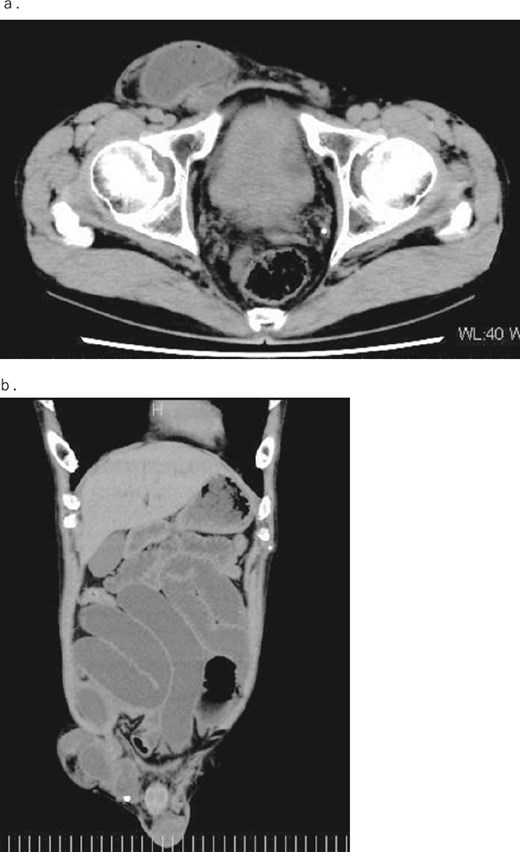

A 54-year-old, normally healthy patient had been experiencing abdominal pain for approximately 6 hours before visiting our hospital. Computed tomography (CT) revealed an incarcerated right inguinal hernia (Fig. 1); therefore, he visited our hospital. At the time of his visit, the pain had disappeared, as had the bulge in his groin. However, he still felt abdominal fullness. A repeat CT scan revealed that part of the prolapsed intestine remained in the groin. Therefore, the patient was admitted immediately and underwent emergency surgery on the same day. Laparoscopic surgery was performed under general anesthesia. Intraperitoneal findings did not confirm intestinal prolapse; therefore, right inguinal hernia repair using a transabdominal preperitoneal (TAPP) technique with placement of a 3DMax Light Mesh (Bard) was conducted. Because the patient also had an incarcerated inguinal hernia, a detailed examination of the digestive tract revealed a diverticulum on the opposite side of the mesentery, 70 cm from the terminal ileum, and dilation of the oral intestine was observed starting from this site (Fig. 2). Considering the possibility that the Meckel’s diverticulum indicated an incarcerated inguinal hernia, the intestine was elevated outside the abdominal cavity through a small abdominal incision to keep away from the mesh. The diverticulum was resected with a Powered ECHELON FLEX 3000 (ETHICON), and the stapler line was buried with a seromuscular suture to complete the surgery. Pathological examination of the diverticulum revealed ectopic gastric mucosa, although no malignancy was noted.

Intraoperative image. (a) Intraperitoneal observation reveals a Meckel’s diverticulum 70 cm from the Bauhin’s valve. (b) The intestinal caliber change is observed before and after the Meckel’s diverticulum.

An incarcerated inguinal hernia caused by Meckel’s diverticulum was reported in the 1700s by the French surgeon Alexis de Littre [3]. A Littre hernia is a rare condition, occurring in 0.09% of inguinal hernias [4] and <1% of complications of Meckel’s diverticulum [4, 5]. Littre hernias most frequently occur in the groin area, although studies have shown occurrence frequencies in the order of thigh (50%), groin (27.6%), and umbilicus (11.2%) [3]. For preoperative diagnosis, radiography is commonly used (56.1%), followed by CT (17.5%) and ultrasound (8.8%) [3], although rather than diagnosing Littre hernias preoperatively, they are generally used to support the need for emergency surgery, as Littre hernias are almost always diagnosed intraoperatively. There are a few reported cases of spontaneous reduction of an inguinal hernia caused by a Meckel’s diverticulum, as in our case. Most naturally reduced inguinal hernias are treated with elective surgery, at which point the dilation of the digestive tract is released, and surgery for the inguinal hernia is performed without exploring the digestive tract. In our case, the incarcerated hernia spontaneously decreased, and an examination was performed to check the blood flow and vitality of the released intestine, which revealed a Meckel’s diverticulum. The Meckel’s diverticulum was located on the opposite side of the mesentery of the small intestine, 70 cm from the ileocecal area. Since the caliber change of the intestine was observed before and after the Meckel’s diverticulum, it was predicted that the same part was the prolapsed intestine of the inguinal hernia.